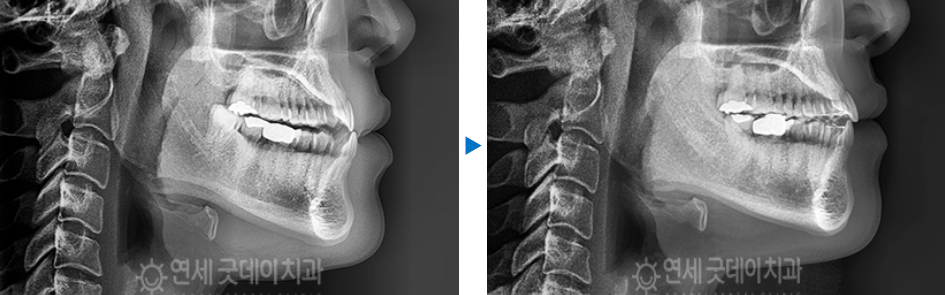

위 사진과 같이 엑스레이로 측면을 촬영하게 되면

위 치아가 아래치아보다 안으로 말려들어간 형상을

볼 수 있습니다.

이는 정상적인 교합과 달리 거꾸로 물리는

‘반대교합’ 양상을 확인할 수 있습니다.

치료 전 - 치료 후

치료 전과 후를 한번에 살펴보게 되면

주걱턱 성향의 전형적인 옆모습이 개선되고,

물리지 않던 송곳니가 잘 물리고 있는

모습을 볼 수 있는데요.

결국엔 모든 치아가 뒤로 감으로써 윗니가

아랫니를 살짝 덮는 정상교합이 완성되었습니다.